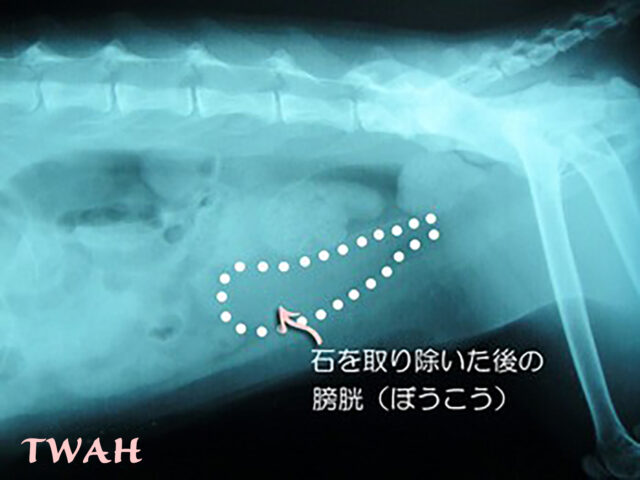

最後の下の画像は、術後の腹部、膀胱のレントゲン写真です。結石はかくにんできません。全て摘り除かれています。

結石はありません。